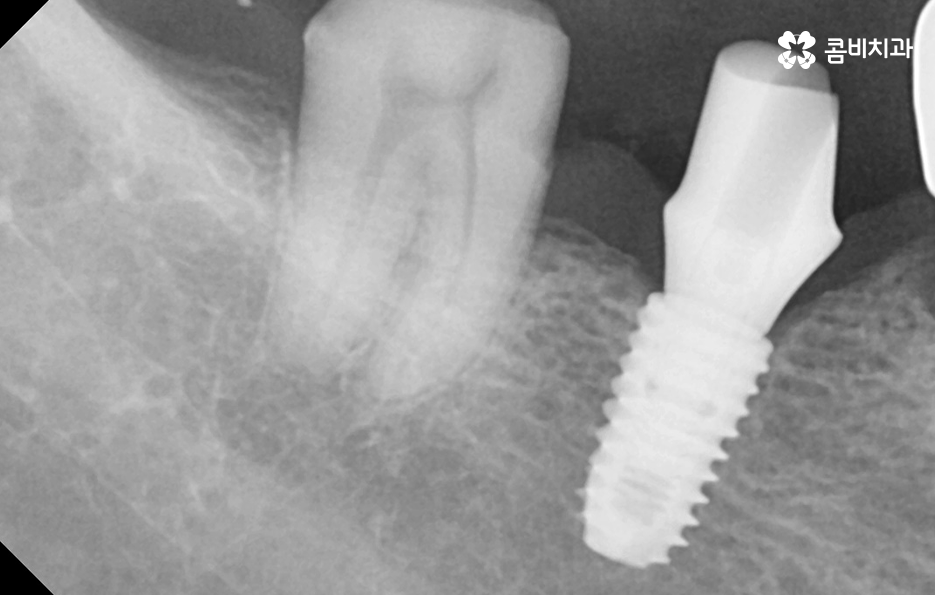

위 사진을 보시면 치아 자체의 노화나 균열도 물론 크지만 잇몸이 내려앉아서 치아의 뿌리 부분이 외부에 노출되어 있는 것을 알 수 있는데요. 노인임플란트 필요로 하는 분들의 치아 상실의 대표적 원인은 충치 부터 오래된 크라운, 치아의 손상 및 균열로 인한 문제도 크겠지만 결정적으로는 치주염으로 인해 잇몸 뼈가 녹고 잇몸 퇴축으로 인한 치아 상실이 노년기에 발생하는 치아 상실의 대표적 원인이 되고 있어요

위 케이스의 노인임플란트 치료의 경우 치아의 균열부터 뿌리까지 깊어진 충치, 치주염 까지 복합적인 이유로 치아를 상실하고 여러 개의 임플란트를 식립한 사례라고 할 수 있는데요. 그래도 아직은 잔존하고 있는 치아가 많기 때문에 이미 상실한 치아에는 노인임플란트 각 위치에 맞게 적절한 치료를 받고 나머지의 자연치아에 대해서는 잘 관리하는 것이 중요한 시점이라 할 수 있어요